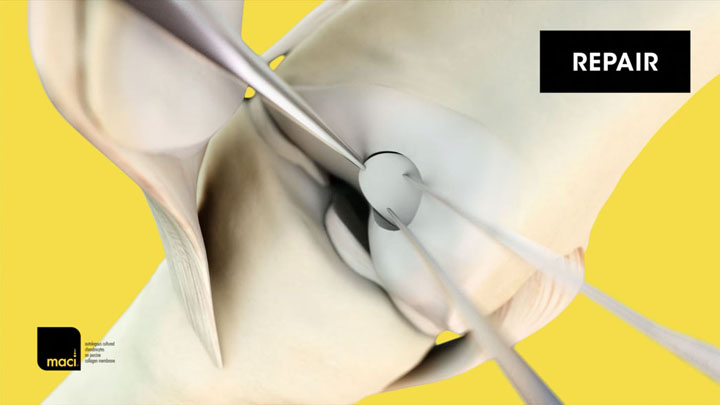

MACI® (autologous cultured chondrocytes on porcine collagen membrane) is an autologous cellularized scaffold product that is indicated for the repair of single or multiple symptomatic, full-thickness cartilage defects of the adult knee, with or without bone involvement.

MACI is intended for autologous use and must only be administered to the patient for whom it was manufactured. The implantation of MACI is to be performed via an arthrotomy to the knee joint under sterile conditions.

The amount of MACI administered is dependent upon the size (surface in cm2) of the cartilage defect. The implantation membrane is trimmed by the treating surgeon to the size and shape of the defect, to ensure the damaged area is completely covered, and implanted cell-side down.